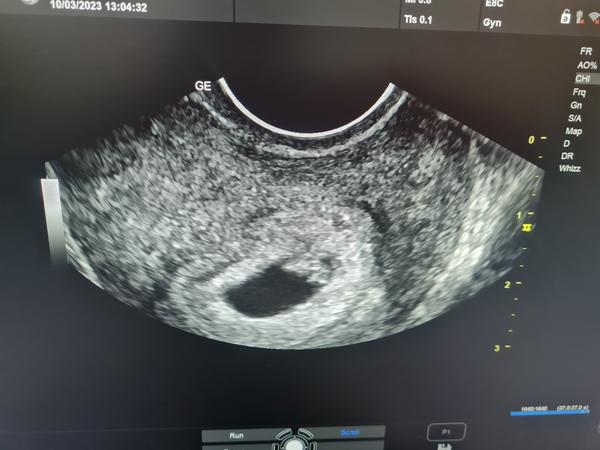

@jasmine_3 ahoj tak to je super, hlavne nech vsetko ďalej pokračuje v poriadku 🙂 ja som dnes začala 9t, mala som trochu spinenie dva krat tak som sa zľakla ale vraj vsetko v poriadku, tak ze dufam ze to tak bude pokračovať 😊 uz vysadzujem aj lieky, a zle jo bolo mi strasne nevoľno o to horšie ze som nezvracala tak ze bolo mi tak cele dni 😅

@viv009 ahoj tak ja ďalšia kontrola v car štvrtok usg tak som zvedavá ako bude. .miestami mam pocit ako keby som nebola tehotna hurá fungujem a potom ako dnes mam pocit že ma prešiel kamión dnes som vstala hore zadkom nálada zla unavená nič sa mi nechce aj keby som chcela len lezim úplne že stavy nenormálne...poraďte niečo na unavu už sa premaham ale nejde to ja co som bola stále aktívna teraz sa cítim ako nejaká lenivá lemra😁..

@katarinaforever ďakujeme tak už by sme mali byť 9tt takze uz sa nevieme dočkať usg a co povie pani doktorka kedy už nemusíme chodiť kmdo car a ze už môžem k svojmu lekárovi...aj vám držíme prateky aby všetko dobre dopadlo 🙏🙏🙏